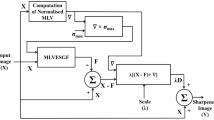

Unsharp Masking (UM) is a popular technique widely used for sharpening medical imagery. However, UM has two operational parameters which have crucial influence on its performance. They are amount (λ) and threshold (α). Improper selection of the threshold and amount will cause noise amplification and overshoot artefact, respectively. A fully adaptive UM with data driven operational parameters, for sharpening Magnetic Resonance (MR) images is proposed in this paper. The proposed sharpening scheme is compared with the homomorphic filter in terms of sharpness of the output image, width of salient edges, feature preservation, saturation and edge quality degradation due to noise. The proposed scheme of UM is found to be superior to homomorphic filter in terms of edge strength and feature preservation and it is free from overshoot artefacts. Modified configuration of UM, proposed in this paper can be used for improving the edge quality of MR images. It can be incorporated as a plug-in in software tools used for the automated analysis of MRI.